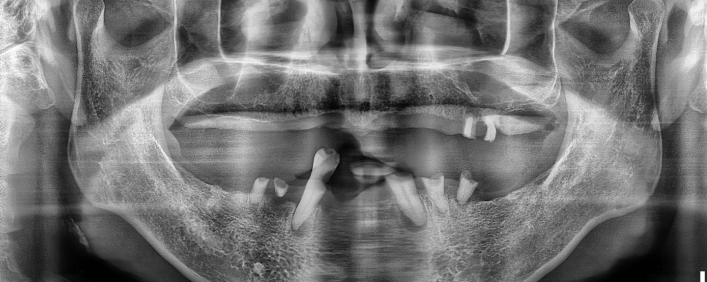

네비게이션 임플란트

0.1mm의 오차 없이, 계획된 위치에 임플란트를 식립합니다.

네비게이션 임플란트(=가이드 수술)은 3D CT를 통해 환자의 구강 내 환경을 정확하게 정밀진단 하여

계획된 위치에 미리 임플란트를 심어 어떤 결과를 얻어낼 수 있는지 컴퓨터 화면에서 시뮬레이션을 할 수 있는 시스템으로

실제 수술 전 구강상태 그대로 모의 수술 과정을 직접 확인할 수 있어 여러 개의 임플란트도 안정적으로 식립할 수 있습니다.

임플란트 치료사례

서울스마트치과는 결과로 증명합니다.

위 치료 사례는 서울스마트치과에서>직접 치료를 받고, 환자 본인의 동의를 얻어 게재된 사진으로 무단 인용, 도용, 재배포 시 민/형사상 책임을 질 수 있습니다.